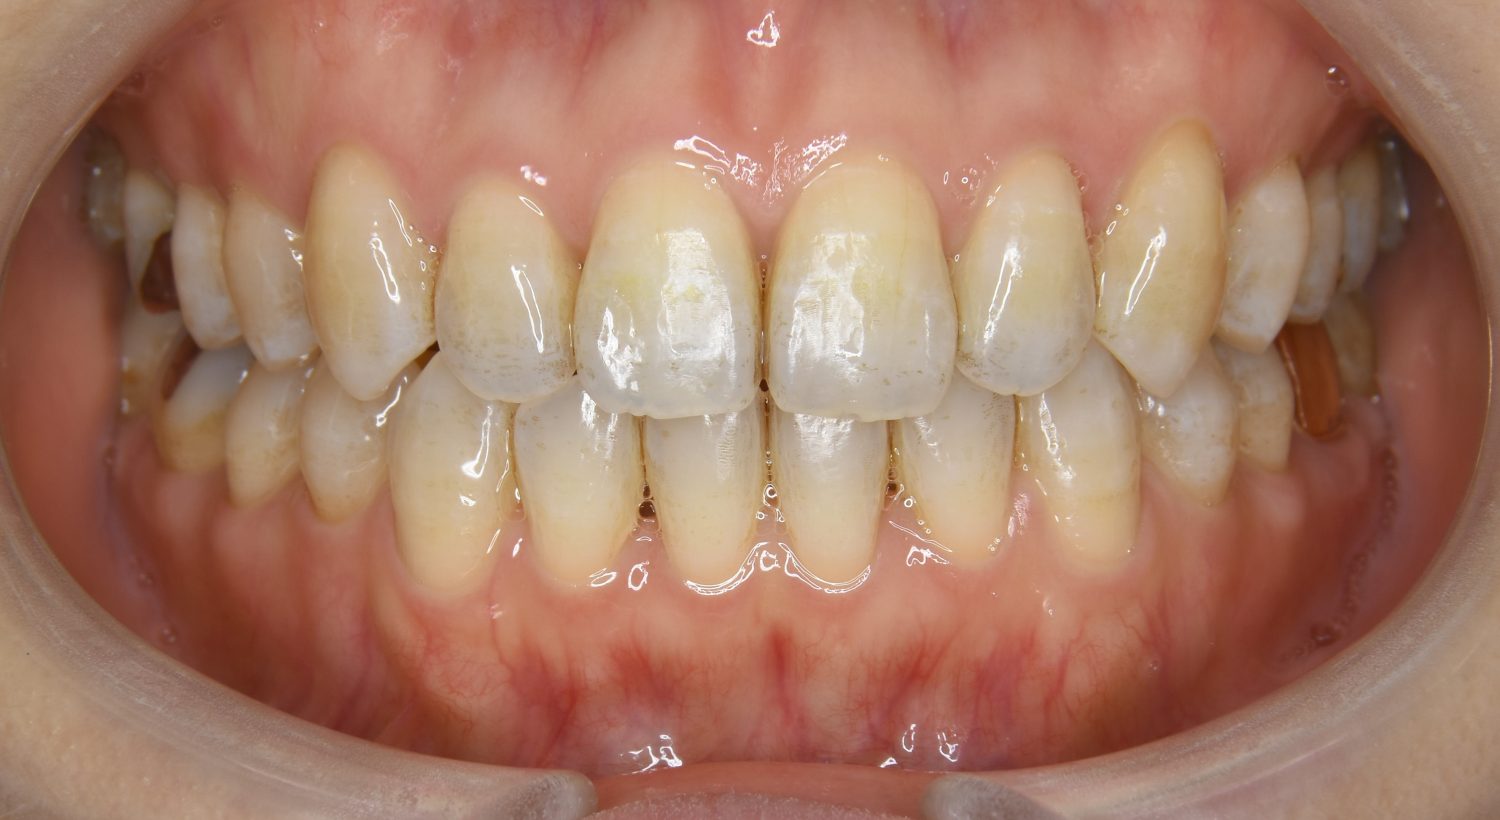

叢生の症例紹介②

Before

After

主訴

歯の凸凹を治したい。

治療内容

アライナー(インビザライン)にて非抜歯で治療を行いました。

治療費

1,150,000 円(税込)

治療期間

26ヶ月

通院回数

14回

想定されたリスク

※歯根吸収、歯肉退縮、歯髄壊死、顎関節症状

※アライナー(インビザライン)は日本の薬機法未承認の矯正装置であり、医薬品副作用被害救済制度の対象外となる場合があります。

上下前歯部に叢生(凸凹)が認められる状態でした。歯列の遠心移動を行うことで機能面および審美面が改善されました。